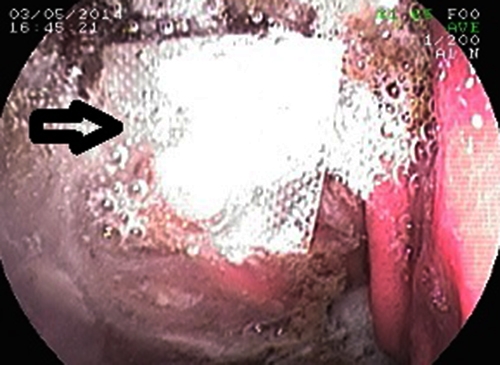

Tin từ BV An Bình (TP HCM), các bác sĩ vừa nội soi cấp cứu gắp ra viên thuốc còn chưa bóc khỏi vỉ cho một bệnh nhân. Nguyên nhân do bệnh nhân có thói quen cắt từng viên thuốc còn trong vỉ để tiện sử dụng, sơ ý bệnh nhân đã uống khi chưa bóc thuốc ra. Ngay sau đó, bệnh nhân buộc phải nhập viện vì thấy nghẹn thở.

Theo các bác sĩ, những ca dị vật đường tiêu hóa là viên thuốc còn trong vỉ rất thường gặp. Có khi thuốc còn mắc kẹt ở thực quản nhưng một số trường hợp viên thuốc lại thoát xuống dạ dày - ruột. Do tác động co bóp của ống tiêu hóa và với các cạnh sắc bén, nhiều trường hợp vỉ thuốc gây thủng thực quản, dạ dày hay ruột rất nguy hiểm, phải mổ cấp cứu.